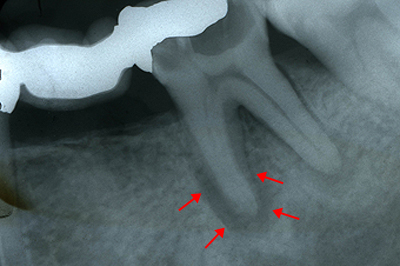

神経まで及んだ虫歯は、歯の根の治療をできるだけ丁寧に行います。

初診時:歯の根の病気で黒くなっています。

6年後:根の周りの黒いところは白くなり、完治済です。